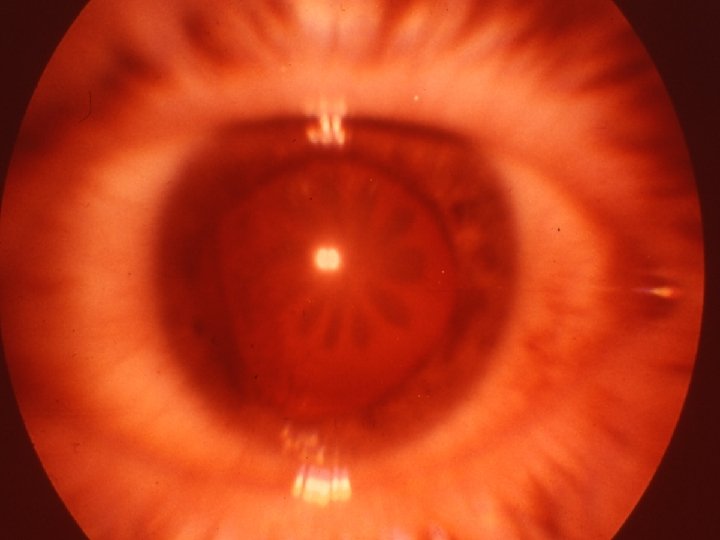

Traumatologie et Brûlures oculaires 2 - Contusions du globe Le syndrôme traumatique du SA Cataracte traumatique Fait suite à un traumatisme violent même sans plaie oculaire Évolution variable, atteinte postérieure en rosace Subluxation Luxation antérieure ou postérieure Consultation pour bilan d’autres lésions associées